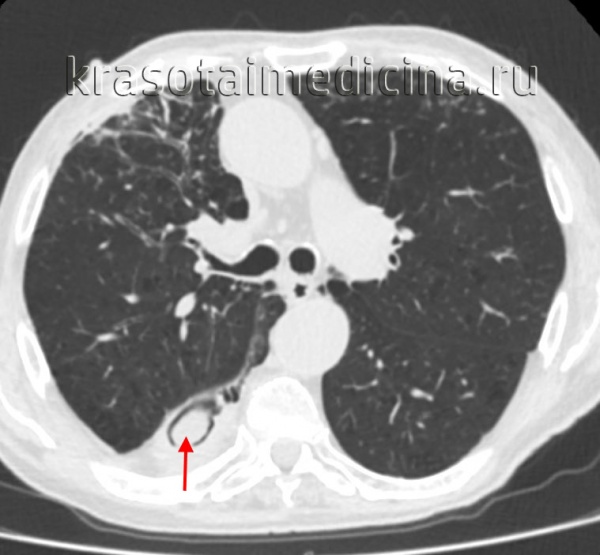

Одиночные или множественные сферические тени обнаруживаются на рентгенограммах и КТ легких, чаще всего располагаются в верхних долях с одной или обеих сторон. Патогномоничным признаком мицетомы является симптом полумесяца - наличие воздушной полосы, которая отделяет большую часть массы гриба от стенки полости. Когда положение тела пациента изменяется, наблюдается внутриполостное движение шарика, образованного аспергиллусом - симптом погремушки.

КТ ОГК. Формирование объема полости в нижней доле правого легкого частично заполнено грибными массами.